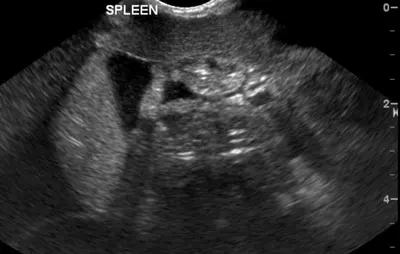

Figure 1: Free abdominal fluid around the spleen visualized with an abdominal FAST examination

An ultrasound image showing the spleen of a veterinary patient, with the organ appearing as a textured structure in shades of gray. The image includes labeled anatomical details, indicating the spleen's position within the abdominal cavity.